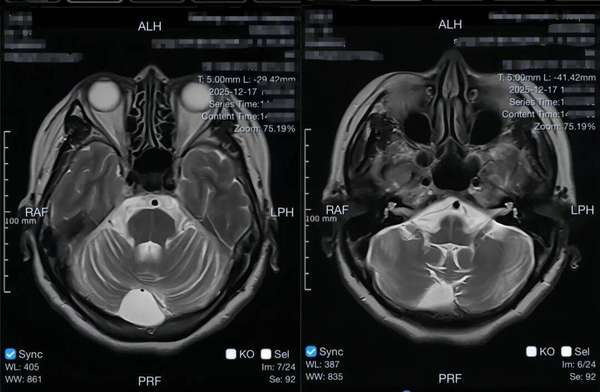

李阿姨的“多系统萎缩”情况非常典型:一开始是眩晕(大多和小脑、血压调节系统受损有关);慢慢又添了走路不稳、小便失禁的症状,颅脑核磁检查提示小脑萎缩、脑桥“十字征”;还有一个很关键的信号——“睡梦中拳打脚踢”,医学上叫快速眼动睡眠期行为障碍。这个症状,可是神经科医生格外重视的早期危险信号。